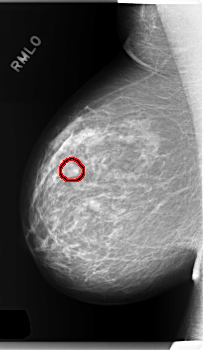

C_0286_1.RIGHT_MLO

RIGHT_MLO LINES 5944 PIXELS_PER_LINE 3448 BITS_PER_PIXEL 12 RESOLUTION 50 OVERLAY

FILE: C_0286_1.RIGHT_MLO.OVERLAY

TOTAL_ABNORMALITIES 1

ABNORMALITY 1

LESION_TYPE MASS SHAPE ROUND MARGINS OBSCURED

ASSESSMENT 3

SUBTLETY 4

PATHOLOGY BENIGN

TOTAL_OUTLINES 1

BOUNDARY